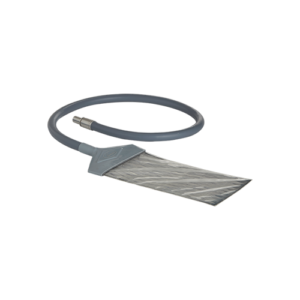

BC 585

Infant/Neonatal Breathing Circuit with Heated Wire for High Flow Oxygen Therapy